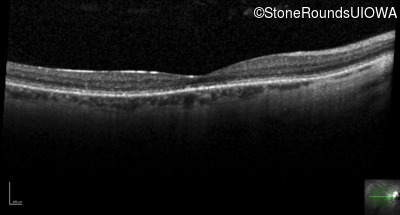

Optical Coherence Tomography - Right - 20/32 -1

Exemplar / OCT Stack